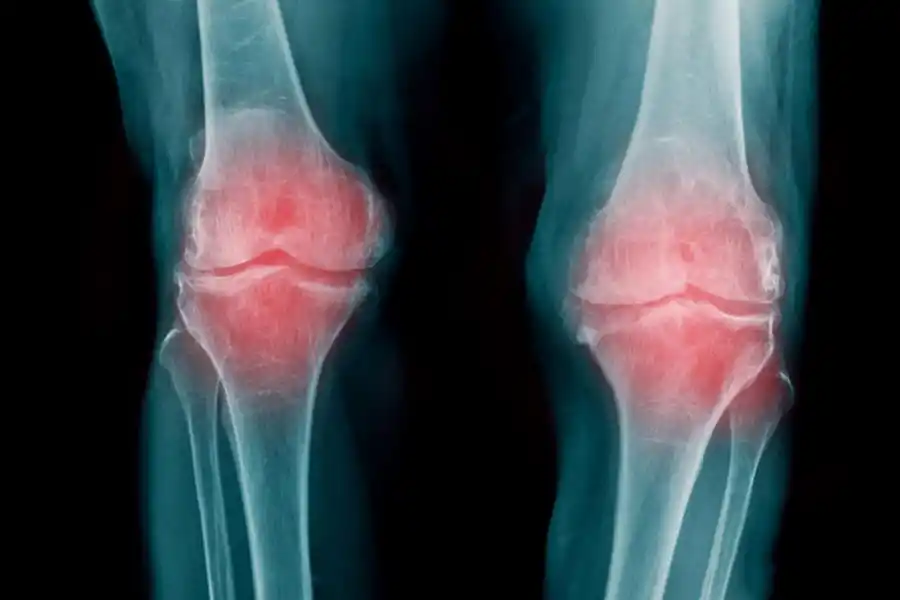

Una de las ventajas para nuestro bienestar que aportan los frutos secos son el alivio a enfermedades degenerativas como la artrosis. En esta afección el cartílago que actúa como amortiguador entre los huesos se desgasta y así estos tejidos comienzan a rozarse entre sí, provocando dolor, inflamación y la limitación del movimiento.

En la artrosis el cartílago que recubre las articulaciones se desgasta.